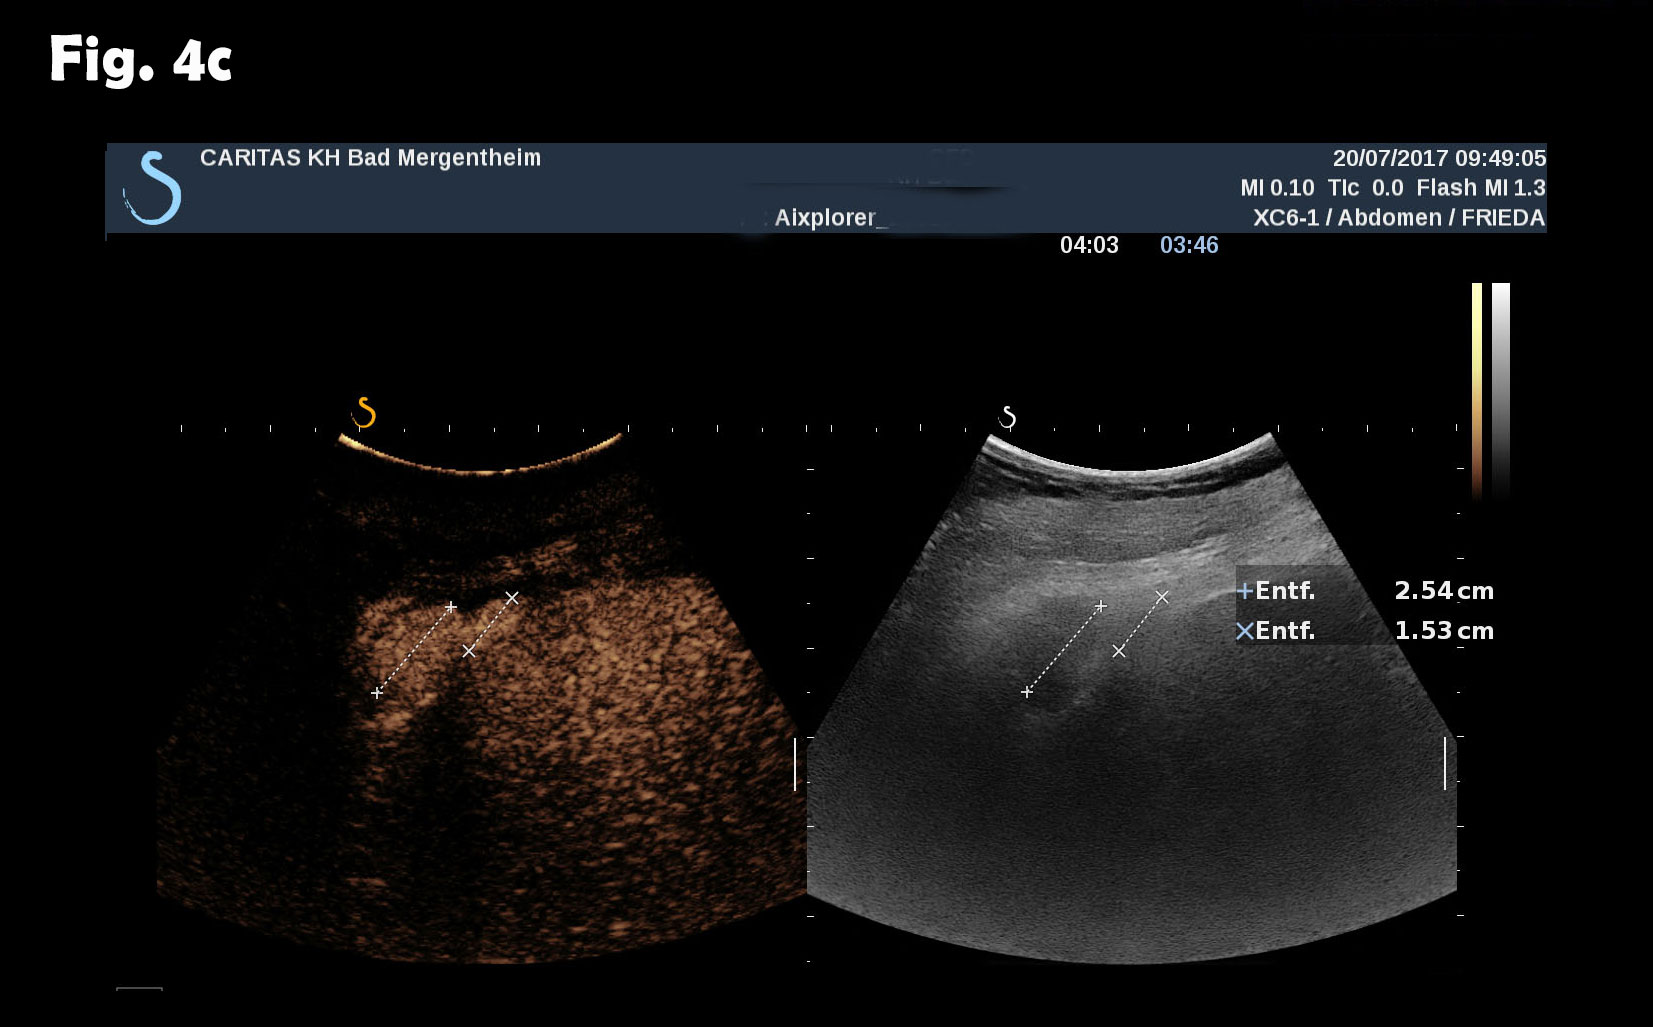

Computed tomography of the chest revealed pneumonic infiltration but was otherwise normal. The endoscopic examination of the upper and lower gastrointestinal tract was normal. Contrast enhanced ultrasound (CEUS) showed arterial and late phase enhancement lasting more than 5 minutes in all examined nodules. After Biopsy the ultrasound examination was performed showing multiple almost echofree but also echogenic round and oval shaped focal peritoneal masses with a size of up to 46 mm [Figure 2-4].

Figure 4: At different abdominal locations more echogenic round oval lesions upt to 30 mm were identified by ultrasound. The lesions were best depicted during the late phase enhancement behind the accessory spleen next to the lesion shown in figure 2 (a) and elsewhere in the abdomen (b). The Figure 3c represents the CT finding shown in figure 1.